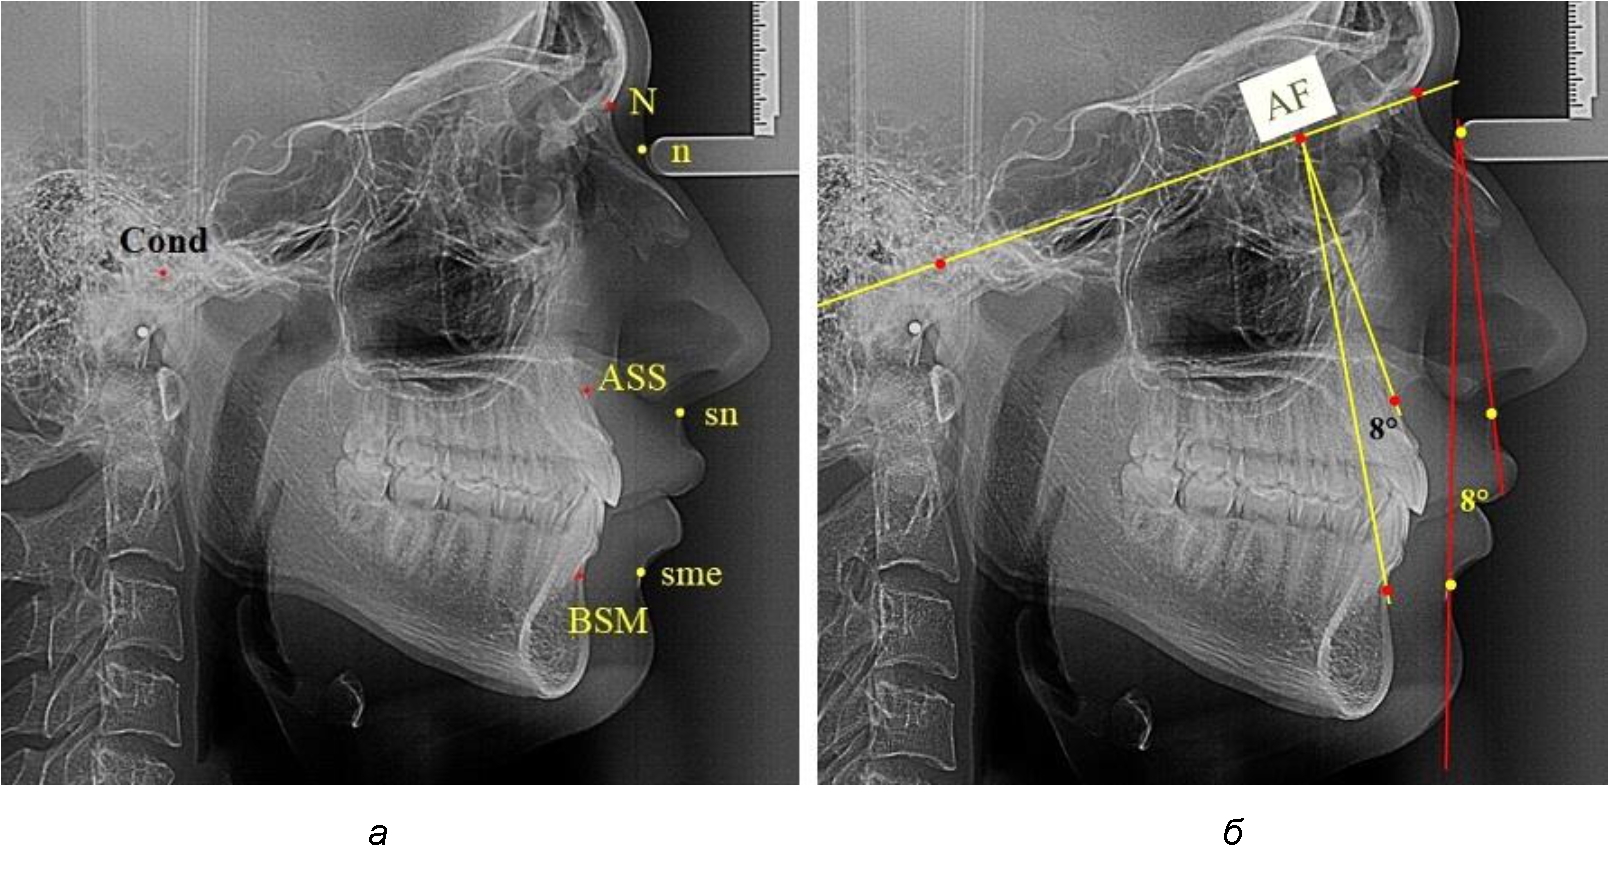

Лицевой межгнатический угол по кожным ориентирам строили соединением точек sn-n-sme, который обозначали как назально-супраменталь-ный угол (рис. 1).

Рис. 1. Точечные ориентиры (а) и основные линии (б) боковой ТРГ для анализа параметров лицевого межгнатического угла

Для построения лицевого межгнатического угла по костным ориентирам использовали в качестве основного ориентира кондилярно-назальную линию, соединяющую точки Cond (верхняя точка суставной головки) и N (место соединения лобной и назальных котей). На передней поверхности челюстей, в наибольшей вогнутости переднего контура, отмечали апикальные точки Downs (ASS и BSM). Из субспинальной точки Downs верхнего апикального базиса ASS строили перпендикуляр к линии Cond–N. Место пересечения линий определяло положение конструктивной апикально-фациальной точки, которую обозначали литерами AF. Точку AF соединяли с супраментальной точкой Downs (BSM) нижнего апикального базиса. Таким образом, костный лицевой межгнатический угол обозначали как угол ASS–AF–BSM. Для определения типов нижней челюсти оценивали величину нижнечелюстного угла. В исследовании выделяли группы людей с нейтральным, вертикальным и горизонтальным типами, которые влияли на положение нижней челюсти.

При фотостатическом анализе использовали профильные фотографии, на которых обозначали точки переднего профильного контура лица, позволяющие определить кожный лицевой межгнатический угол n–sn–smе, который, так же как и при телерентгенографичесом исследовании, обозначали как назально-супраментальный угол (рис. 2). Угол t–n–sn определял типологические варианты лица. Величина угла в 80° характерна для людей с нормопозицией верхней челюсти. Антепозиция верхней челюсти определялась увеличением угла, а ретропозиция – уменьшением. Данные типы лица также оказывали влияние на положение нижней челюсти. Величину угла нижней челюсти использовали в качестве типологической оценки ее роста.

Рис. 2. Точечные ориентиры (а) и основные линии (б) профильного снимка лица для анализа параметров лицевого межгнатического угла

Средняя величина лицевого межгнатического угла, измеряемого на фотографиях в профиль, составляла (7,29 ± 1,28)° и показатели практически не отличались от аналогичных параметров, полученных при анализе телерентгенограмм, что также подтверждает объективность предложенных методов исследования (рис. 4).

Рис. 4. Параметры лицевого межгнатического угла при нормопозиции (а), антепозиции (б) и ретропозиции (в) гнатического отдела лица

В группе людей при нормопозиции челюстей величина лицевого межгнатического угла была несколько меньше и составляла (8,12 ± 0,41)°. При антепозиции величина угла была несколько меньше и составляла (7,0 ± 0,52)°.

В группе людей с ретропозицей величина лицевого межгнатического угла была больше, чем при других типах и составляла (8,25 ± 0,43)°. Достоверных различий не отмечено, что позволяет величину лицевого угла от 6 до 10° рассматривать как оптимальные показатели для физиологического расположения нижней челюсти по отношению к положению верхней челюсти.